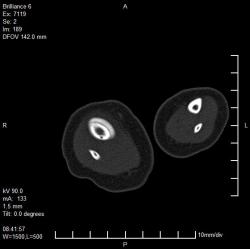

Ребенок 4 месяца. Отмечается увеличение размеров голени в течение нескольких месяцев после рождения. Травму, как бытовую, так и родовую мать отрицает. Мать обследована на ЗППП, в том числе сифилис. Выполнили рентгенографию, затем - КТ. Сначала думали о переломе и гипертрофической костной мозоли вследствие отсутствия иммобилизации, на реконструкции КТ видна как будто бы линия перелома (канал кровеносного сосуда?). Однако отсутствие положительной динамики со временем ("мозоль" не уменьшается) настораживает в плане возможной опухоли. Взяли открытую биопсию, материал пока еще в работе.

Опубликовано Валентин Катенёв в Сб, 01/24/2009 - 22:05. # Уважаемый коллега! Я совершенно не разбираюсь ни в КТ, ни в МРТ, ни в СКТ, ни в УЗИ. Но мне кажется, что в данном случае - см. вложение 11 четко дифференцируется косонаправленная прерывистость кортикального слоя б/берцовой кости - перелом? По всей видимости и гиперостоз и прочие изменения вызваны не диагностированным переломом.

Опубликовано Валентин Катенёв в Вс, 01/25/2009 - 14:28. # Уважаемая коллега! Полностью согласен с Вами по поводу "отслойки периостальных наслоений", возможно даже за счет излившейся крови (гематома). Такая махровость "периостальных наслоений" вполне может быть объяснена отсутствием иммобилизации, ибо ребенок постоянно двигает ножкой.